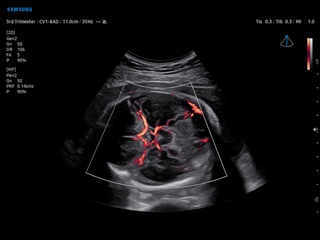

Atlas of ultrasound images - obsterics

In the section "Оbsterics" of atlas the results of ultrasonic examinations of pregnant women with different durations of gestation are represented. Here you can see images of internally organs, cerebrum, cordis and the sex of the fetus, the sonograms of multiple pregnancy, the blood flow in placenta and umbilical cord, defects of fetal`s development, etc.